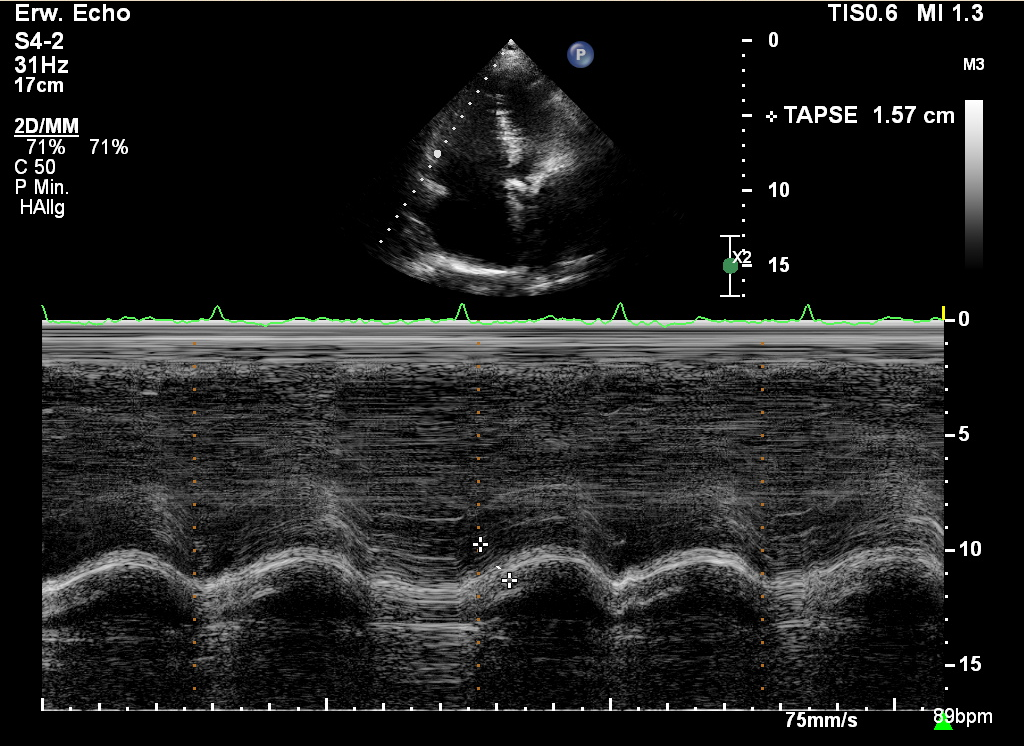

heutiger Einsatz des M-Mode

• TAPSE

• AVPD (=MAPSE)